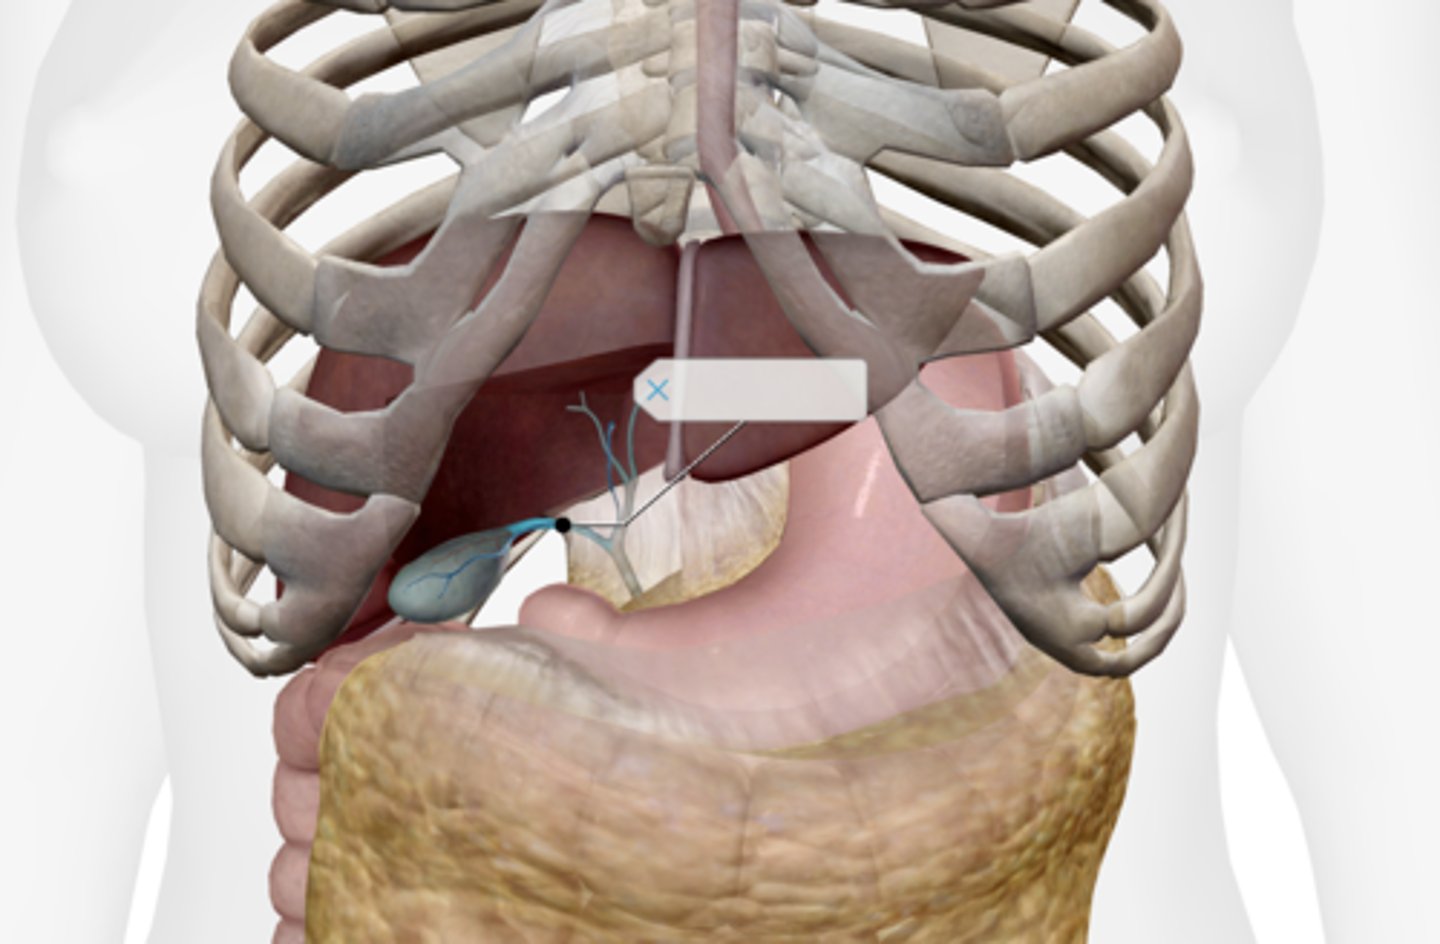

Gallbladder

Cystic duct

Common hepatic duct

Common bile duct

Pancreas

Main pancreatic duct (duct of Wirsung)

Accessory pancreatic duct (duct of Santorini)

Liver

Hepatic artery & vein

Falciform ligament